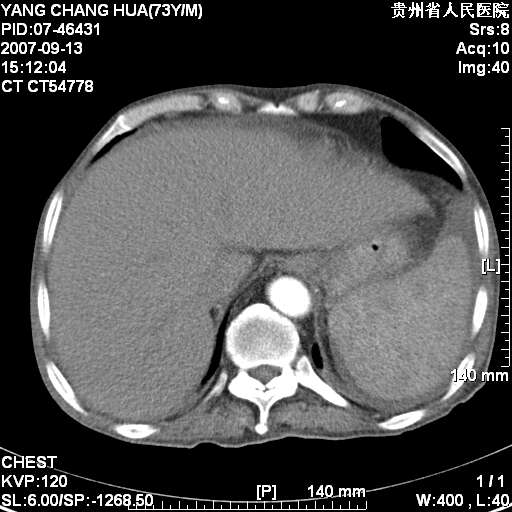

图像没有传全。肺部为感染性病灶;肺囊肿;双侧胸腔积液;肝脾肿大;腹水。

双肺部为感染性病灶.双侧胸腔积液;肝脾肿大;腹水.

双肺部为感染性病灶.双侧胸腔积液;肝脾肿大;脾脏密度不均,不除外脾侵润?腹水.

图片不全.就这几张图片.无法诊断淋巴瘤的,我考虑:双肺部为炎性病灶.双侧胸腔积液;肝脾肿大;腹水

肝脾肿大。

少量腹水。

双肺散在斑片状及多发小结节状阴影,边缘模糊,双上肺野明显,双侧胸膜腔少量积液,纵隔及肺门区未见明显肿大淋巴结,肝脾肿大,脾内见多发低密度区,结合临床考虑恶性淋巴瘤(肺内表现为肺炎肺泡型),单看影像表现,肺结核不能排除。建议结合实验室检查或表浅淋巴结活检。

肺部为;恶性淋巴瘤;双侧胸腔积液;肝脾肿大;腹水。